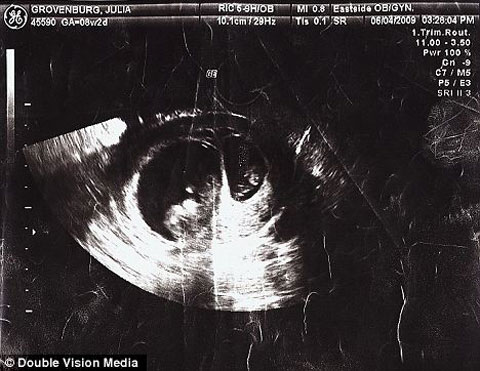

Cô không sinh đôi nhưng cô có 2 đứa trẻ Sau khi không thể có con trong 3 năm, Julia Grovenburg và chồng cô Todd đã xem xét đến việc nhận nuôi một đứa trẻ nước ngoài để thỏa mãn ước mơ về một gia đình của họ. Tuy nhiên, vào một buổi chiều tháng 7/2009, họ đã nhận được tin vui. Họ còn ‘sốc’ hơn khi cô đã mang thai 2 lần trong vòng 2 tuần. Cô là một trong 11 phụ nữ trên thế giới được cho là đã thụ tinh dị bội, nghĩa là 2 đứa trẻ được thụ thai vào 2 thời điểm khác nhau, được sinh ra cùng ngày nhưng về mặt y học, chúng không phải là trẻ song sinh.

Hiện tại, Julia đã sinh và đang khá vất vả với việc nuôi dưỡng 2 đứa trẻ không phải song sinh nhưng được sinh cùng lúc. Các bác sĩ đã rất ngạc nhiên khi quan sát hình ảnh siêu âm, chính xác là một bào thai lớn hơn bào thai kia và họ không thể giải thích được điều gì đang xảy ra trong tử cung của chị Grovenburg. “Trong 30 năm làm nghề, bác sĩ của chúng tôi chưa từng thấy một trường hợp như vậy” – ông Grovenburg nói. “Ông ấy nói ‘Julia, cô không sinh đôi nhưng cô có 2 đứa trẻ’”. “Ông ấy thấy tin này quá kì lạ, giống như một đột phá y học mà ông ấy đã phát hiện ra”. Nhịp tim và hình ảnh siêu âm cho thấy 2 đứa bé cách nhau khoảng 2,5 tuần.